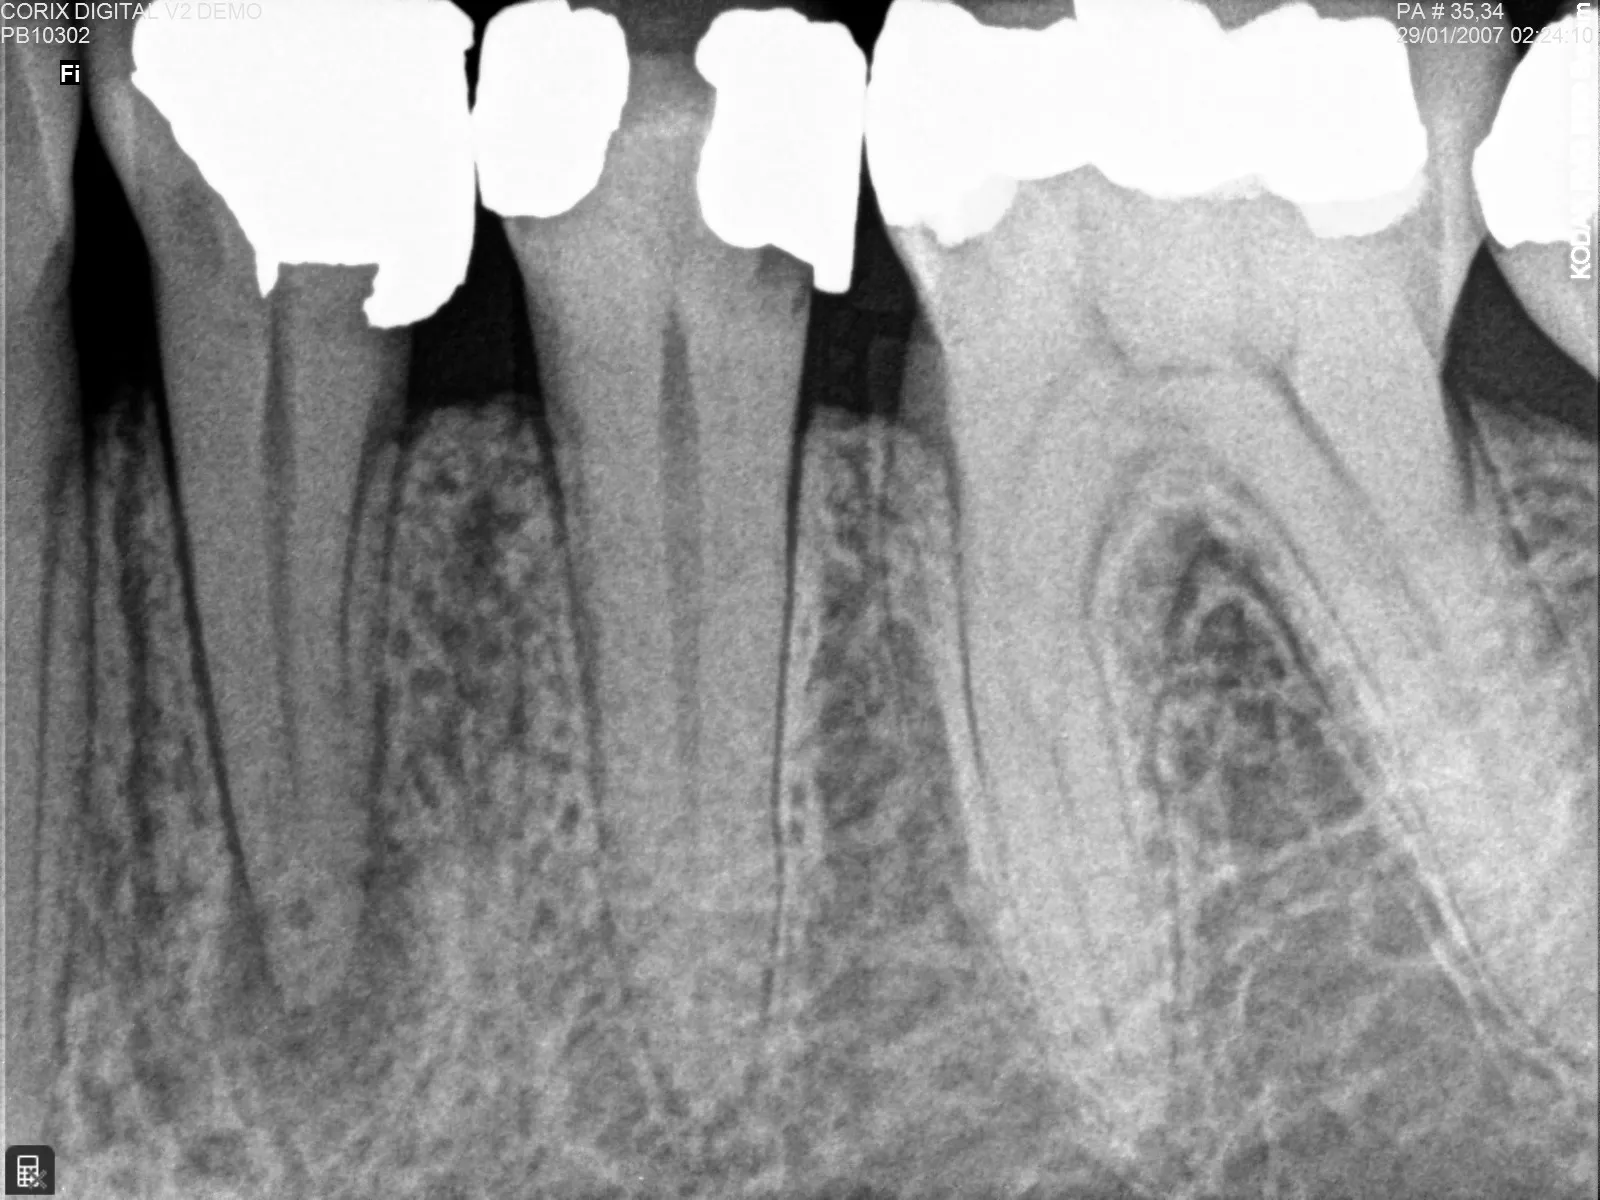

El uso adecuado de los equipos de rayos X dentales periapicales, especializados en radiografías periapicales, se ha consolidado como una herramienta indispensable en la práctica odontológica y en la odontología veterinaria. Estos dispositivos permiten obtener imágenes diagnósticas de alta precisión de dientes,